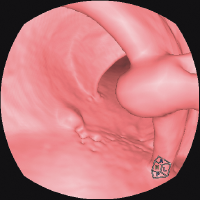

Специальная программа HIMAR для подавления влияния на изображения включений с большим КТ числом даёт возможность визуализировать области и ткани, прилежащие к металлическим объектам, например имплантам.